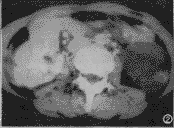

囊性畸胎瘤:9例以囊性为主且含有少量CT值为-50~-110HU的脂肪影及斑块状钙化或骨化影,可单房或多房,大小8cm×9cm×10cm~12cm×13cm×15cm(图1);1例为巨大均匀多房囊性肿块,无脂肪及钙化影。本组病例均表现为壁厚薄不均,增强后壁明显强化,与周围组织界限清楚,形态尚规则,相邻组织受压移位。

图1 囊性畸胎瘤。以囊性为主且含有少量CT值为-50~-110HU的脂肪影(箭头示)及斑块状钙化影(三角箭头示)